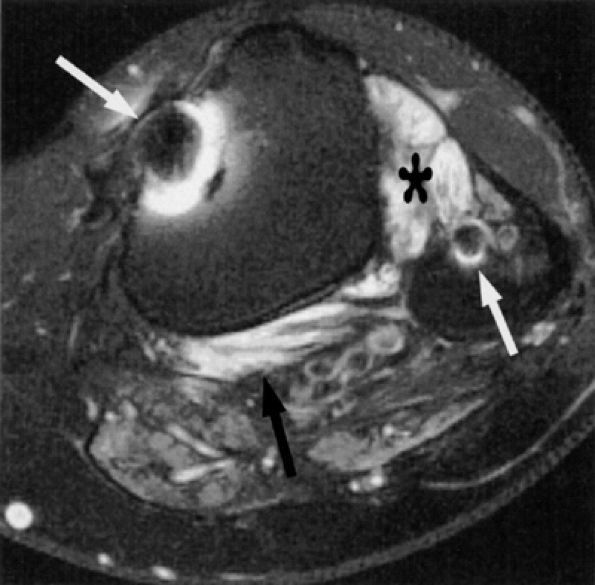

FIGURE 6.49 ● Tarsal tunnel syndrome and medial plantar nerve denervation edema due to proliferative synovitis. (A) Axial T2-weighted image demonstrates a synovial mass (asterisk) in the tarsal tunnel. (B) Sagittal T2-weighted fat-suppressed image illustrates denervation edema in the flexor digitorum brevis muscle (asterisk). Note associated osteoarthritic changes in the anterior tibiotalar joint (arrow).

|